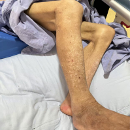

5.入院查体:体温: 38.5℃,脉搏:104次/分,呼吸:21次/分 ,血压:132/80mmHg。神志清楚,双肘关节皮肤见3*3cm,骶尾部皮肤见4*3cm、8*5cm,左足跟见4*4cm压疮皮损,表面无渗血、渗液;桶状胸,肋间隙变宽,胸骨无压痛,无三凹征。双侧呼吸运动对称,呼吸频率21次/分,双侧触觉语颤传导减弱,语音传导减弱,无胸膜摩擦感,双肺叩诊过清音,双肺呼吸音低,双肺闻及中、粗湿啰音,可闻及哮鸣音。心界扩大,心率104次/分,心律齐,各瓣膜区未闻及病理性杂音,无心包摩擦音;腹软,无反跳痛、肌紧张,未触及包块,肝肋下未触及,脾肋下未触及,双下肢中度水肿,右下肢皮肤见暗褐色出血点,右足大趾可见损伤创面、结痂(图1)。

图1.患者右趾创面结痂及右腿皮疹